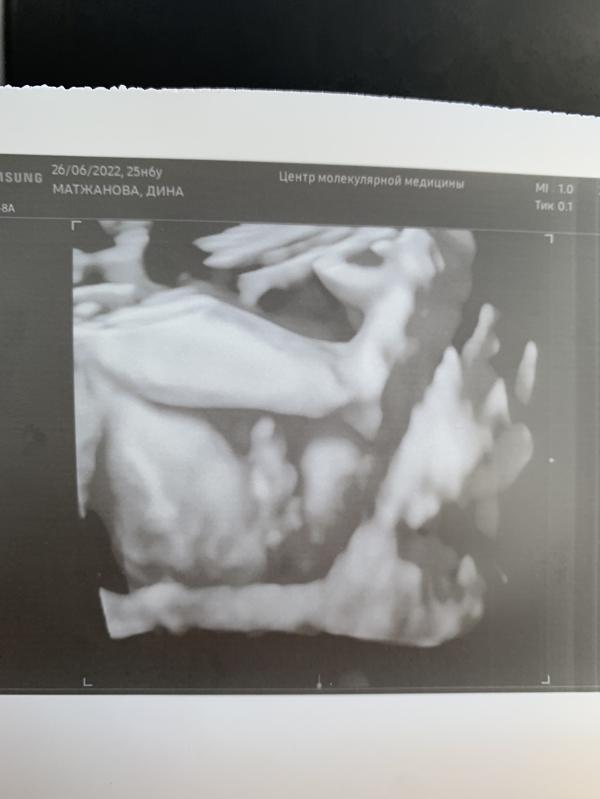

Мой мужичок 💪🏻 25 и 6 дней сделали 3 д узи. Плацента поднялась. Вес 1 кг🙏

Да четко видно было личико

Ого как поймали фото 🤣